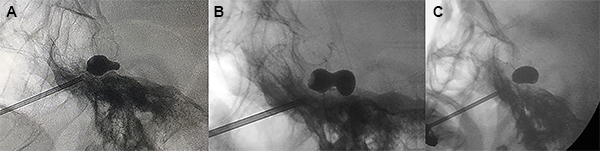

El balón con una jeringa de insulina previamente cargada con contraste radiológico (Iopamidol 612,4 mg /ml) fue lentamente insuflado usualmente entre 0.5 a 1 ml hasta obtener un balón en forma de pera (Figura 7A), o en reloj de arena en tamaño completo (Figura 7B). Se mantuvo insuflado por 60 segundos.

Figura 7: Formas de balón. (A) Pera, (B) Reloj de arena, (C) Oval.

La forma de pera indica que la punta del balón se encuentra dentro del poro trigeminal, que es donde debe estar para comprimir el nervio trigémino adecuadamente. Esta forma de pera correspondería a la anatomía interna de la cavum de Meckel y es indicador que está comenzando a sobresalir del cavum de Meckel hacia el poro trigeminal.

La forma de reloj de arena corresponde cuando la punta del catéter a atravesado parcialmente el poro trigeminal hacia la fosa posterior y el balón se infla parte dentro del cavum de Meckel y parte dentro de la fosa posterior. El término reloj de arena se asigna a formas en las que se identificó un istmo con un diámetro menor entre 2 partes redondas del balón con un diámetro mayor.

Cuando el balón es de forma oval (Figura 7C), redonda, elíptica o irregular, se desinfló el balón y la aguja fue retirada y reposicionada, inclusive se puede cambiar de catéter Fogarty hasta lograr la forma de pera o de reloj de arena, en caso de no ser posible por lo menos se debe lograr la forma oval. En estos casos generalmente se terminó insuflando entre 1.5 a 3 minutos.

La forma oval o redonda pueden aparecer debido a un cavum de Meckel grande, poca cantidad de contraste o una posición incorrecta de la punta del catéter. En la forma elíptica, el catéter está fuera del cavum de Meckel, en posición lateral infratemporal.